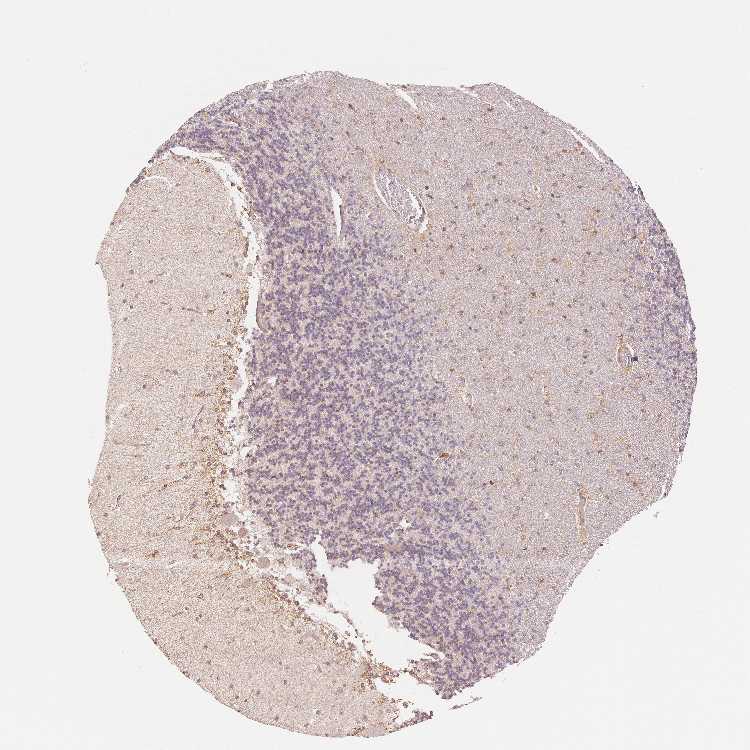

CEREBELLUM - Antibody stainingi

Antibody staining in the annotated cell types in the current human tissue is reported as not detected, low, medium, or high, based on conventional immunohistochemistry profiling in selected tissues. This score is based on the combination of the staining intensity and fraction of stained cells.

Each image is clickable and will lead to virtual microscopy that enables deeper exploration of all samples and also displays staining intensity scores, fraction scores and subcellular localization as well as patient and tissue information for each sample.

Antibody HPA043134Antibody HPA050402

Purkinje cells MediumNot detected

Cells in granular layer LowNot detected

Cells in molecular layer Not detectedNot detected